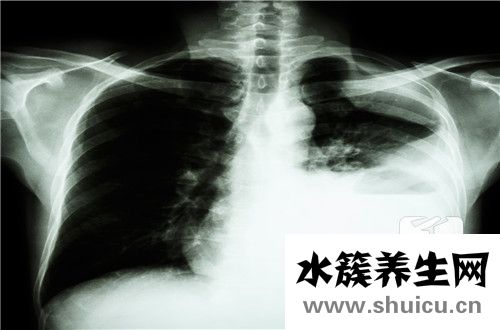

肺部這個器官是人體的呼吸器官,如果吸入的空氣中含有大量的病毒和細菌,就會導致肺部出現感染,正常情況下肺部感染患者是需要進行住院治療的,如果感染的范圍比較小,可以通過服用藥物治療的方式,肺部感染會讓患者出現呼吸困難和發燒等等癥狀,那么肺部感染需要住院多久呢?

第一,肺部感染需要住院多久呢?肺部感染住院的時間與病情有關,一般最少都要將近一周時間。如果有肺部感染,建議您今早到醫院就診,以防病情進展。肺炎為細菌、病毒或支原體感染引起。臨床可表現為發燒伴有咳嗽、咳痰、胸痛等癥狀。 肺炎的治療療程為7到14天。至于費用方面,每個醫院應用的藥物不盡相同,收費標準也不完全一樣,以當地收費標準為準。

第二,肺部感染的癥狀:在沒有呼吸道疾病以及沒有受到過敏的情況下,時常感到呼吸出現困難,喘不過氣來。身體的體溫變高,出現身體發熱的現象,同時可能伴有咳嗽、發燒等癥狀,嚴重時會出現心前區以及胸痛的癥狀。精神狀態變差,反應力變慢,無法集中注意力進行正常的工作與學習。

第三,肺部感染的原因:由于肺部屬于人體的呼吸道,而且空氣會直接接觸到肺部,若是空氣中具有細菌,就會經過呼吸道(口、鼻)進入到肺部,這個時候肺部就被細菌感染到。在身體感冒、發燒的時候,由于人體的組織機能會受到影響,導致身體的抵抗力與免疫力下降,這個時候很容易出現肺部感染。由于身體過于疲勞,身體負荷過重就會導致機體免疫力下降,從而肺部就會因此容易受到感染。

預防肺部感染的方法:是否會出現肺部感染,這個跟個人的體質有著很大的關系,所以在平時要注意加強身體的鍛煉,增強機體的免疫力和機體的抗病能力。在日常生活之中注意環境的衛生,在病毒高發期時,出門活動的時候可以帶上口罩,可以預防空氣中的細菌進入呼吸道。在飲食方面也要多加注意,合理安排飲食結構,多吃富含維生素B和氨基酸的食物,如新鮮蔬菜水果、谷類、蛋類等。